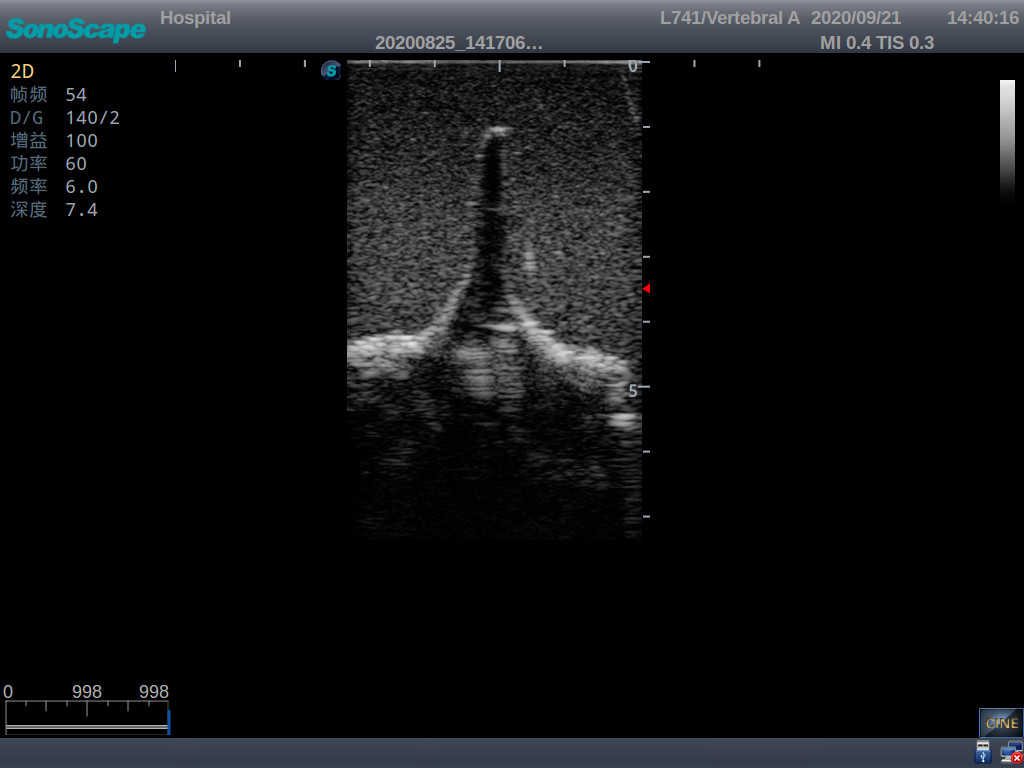

Adult Lumbar Puncture Ultrasound Training Model

This model is an ideal choice for ultrasound-guided adult lumbar puncture training with true-to-life skin feel and touch, accurate anatomical structures as well as real clinical ultrasound images. Realistic resistance to needle tips and correct landmarks provide excellent hands-on experience.

Accurate anatomical structure of L1-L5 and the vertebral canal

2)  Real clinical ultrasound images

3)  Compatible with various real ultrasound machines